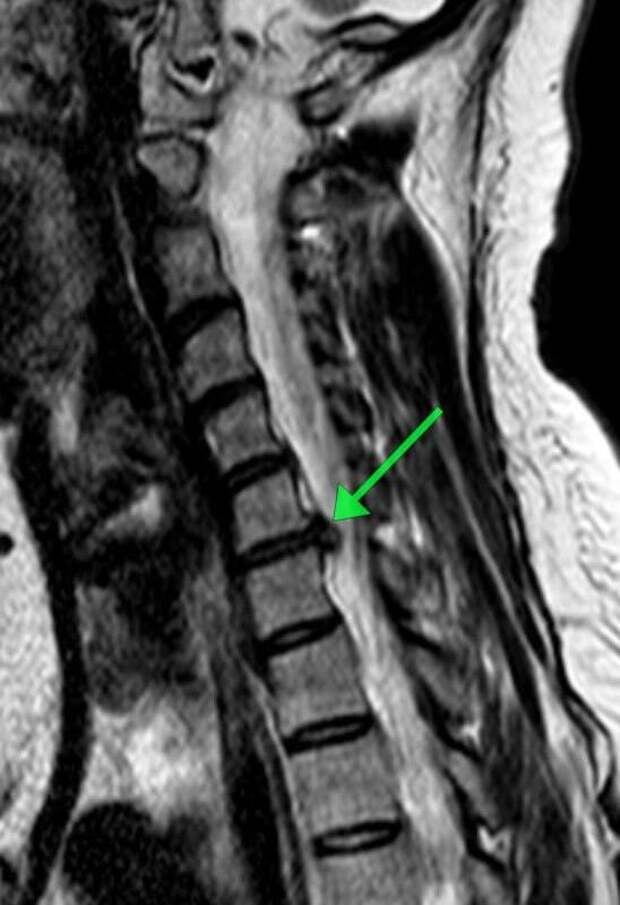

Пациентка обратилась с жлобами на изматывающую боль в руке. Ей провели МРТ, которое показало, что в шейном отделе сформировалась грыжа размером 8 мм.

По словам медиков, образование сдавливало спинномозговой канал и корешковое отверстие, угрожая двигательной функции."Мы провели сложнейшее микрохирургическое вмешательство, в ходе которого удалили грыжу и стабилизировали позвоночник с помощью современного импланта", - рассказал нейрохирург Николай Карпов, отметив, что операция длилась два часа 20 минут.